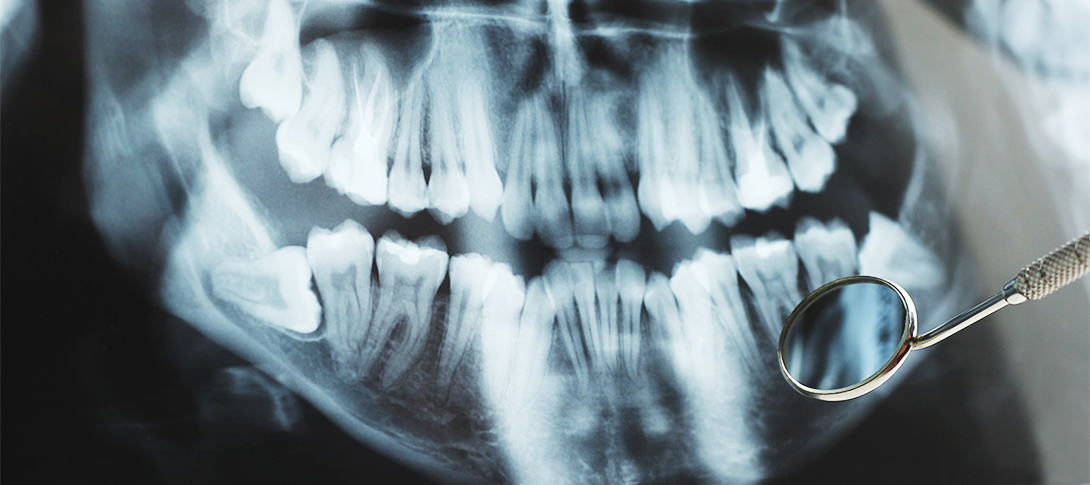

흔히 사랑니라고 부르는 어금니의 제 3대 구치를 말하며, 구강 내 가장 늦게 나오는 치아입니다.

사랑니는 위아래턱 좌우에 한 개씩 모두 4개가 됩니다.

약 7%의 사람에게는 사랑니가 아예 없기도 하며, 입안에 가지고 있거나 나오게 되면 그 개수는 1개에서부터 4개까지 사람마다 모두 다르답니다.

사랑니가 정상적으로 나와서 유지관리가 잘 된다면 사용하는데 있어서 아무 문제가 되지 않지만, 치열의 가장 안쪽 끝에서 공간이 부족한 상태에서 자리를 잡은 경우가 많기 때문에 관리에 어려움이 많아 다양한 질환을 일으킬 수 있습니다.

사랑니의 여러가지 형태

TYPE 01원심경사 매복각도를 가지고 숨어있는 사랑니

TYPE 02수평 매복수평으로 숨어있는 사랑니

TYPE 03수직 매복수직으로 숨어있는 사랑니